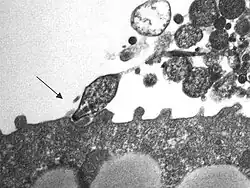

Mycoplasma pneumoniae – mała, atypowa bakteria całkowicie pozbawiona ściany komórkowej. Pojedyncze komórki Mycoplasma pneumoniae mogą przyjmować kształty od form kulistych lub gruszkowatych do rozgałęzionych włókienek. Wielkość form kulistych waha się od 0,3 do 0,8 mikrometrów, natomiast długość form włókienkowatych może dochodzić nawet do kilkudziesięciu mikrometrów.